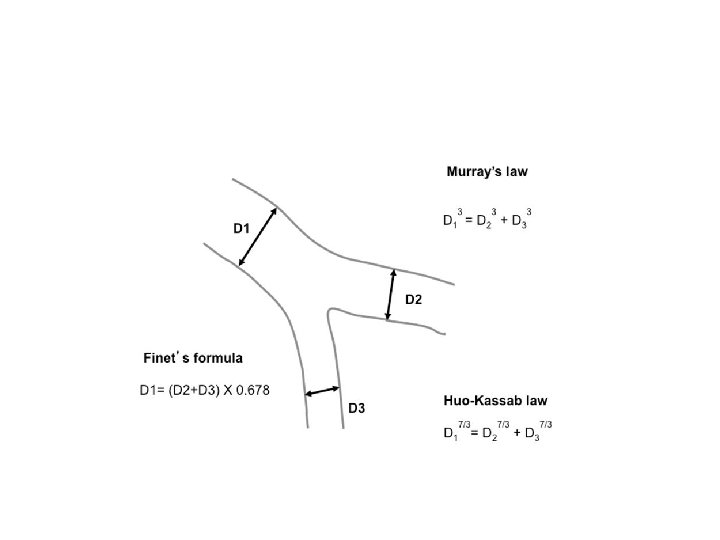

Ramifications of coronary tree follow minimal energy cost in providing myocardial blood flow Finet's law